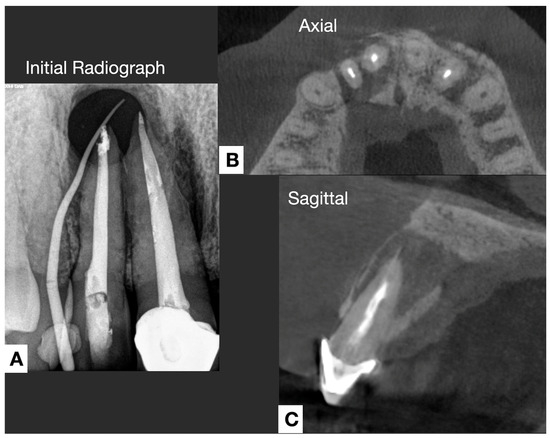

4.3. Radiographic Assessment

- Advancements in imaging techniques, such as AI-assisted CBCT analysis, to enhance the detection of persistent periapical infections and mineralized apical biofilms.

- Yusof, N.A.M.; Harun, N.; Reduwan, N.H.; Al-Bayaty, F.; Ariffin, F. Role of Cone Beam Computed Tomography in Leading to the Finding of Actinomycosis Mimicking Periodontitis. J. Int. Dent. Med. Res. 2020, 13, 4. [Google Scholar]

- Petitjean, E.; Mavridou, A.; Li, X.; Hauben, E.; Cotti, E.; Lambrechts, P. Multimodular assessment of a calcified extraradicular deposit on the root surfaces of a mandibular molar. Int. Endod. J. 2018, 51, 375–385. [Google Scholar] [CrossRef]